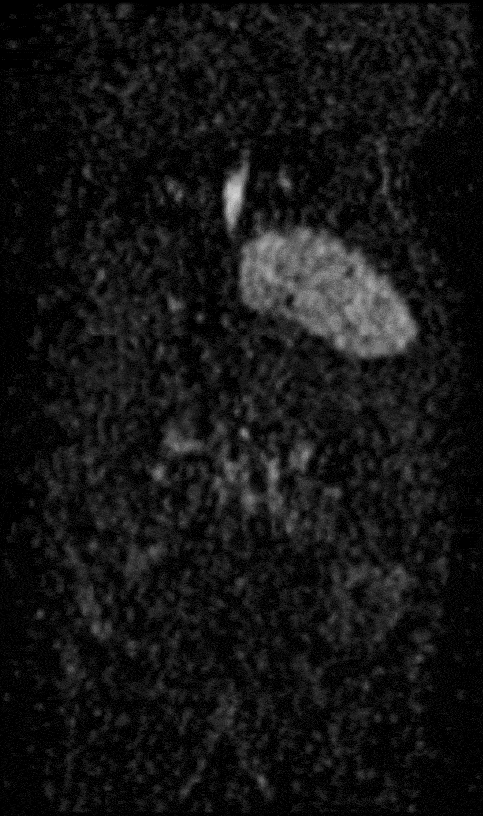

Monitoring the growth of xenograft tumor grown in the mouse hindlimb is identified with T2-weighted images. Segmentation of tumor region of interests (in red) on each tumor-containing slice allows accurate volume quantification. Image Credit: Scintica Instrumentation Inc

Hindlimb tumor growth: Monitoring the growth of xenograft tumor grown in the mouse hindlimb is identified with T2-weighted images. Segmentation of tumor region of interests (in red) on each tumor-containing slice allows accurate volume quantification. Image Credit: Scintica Instrumentation Inc